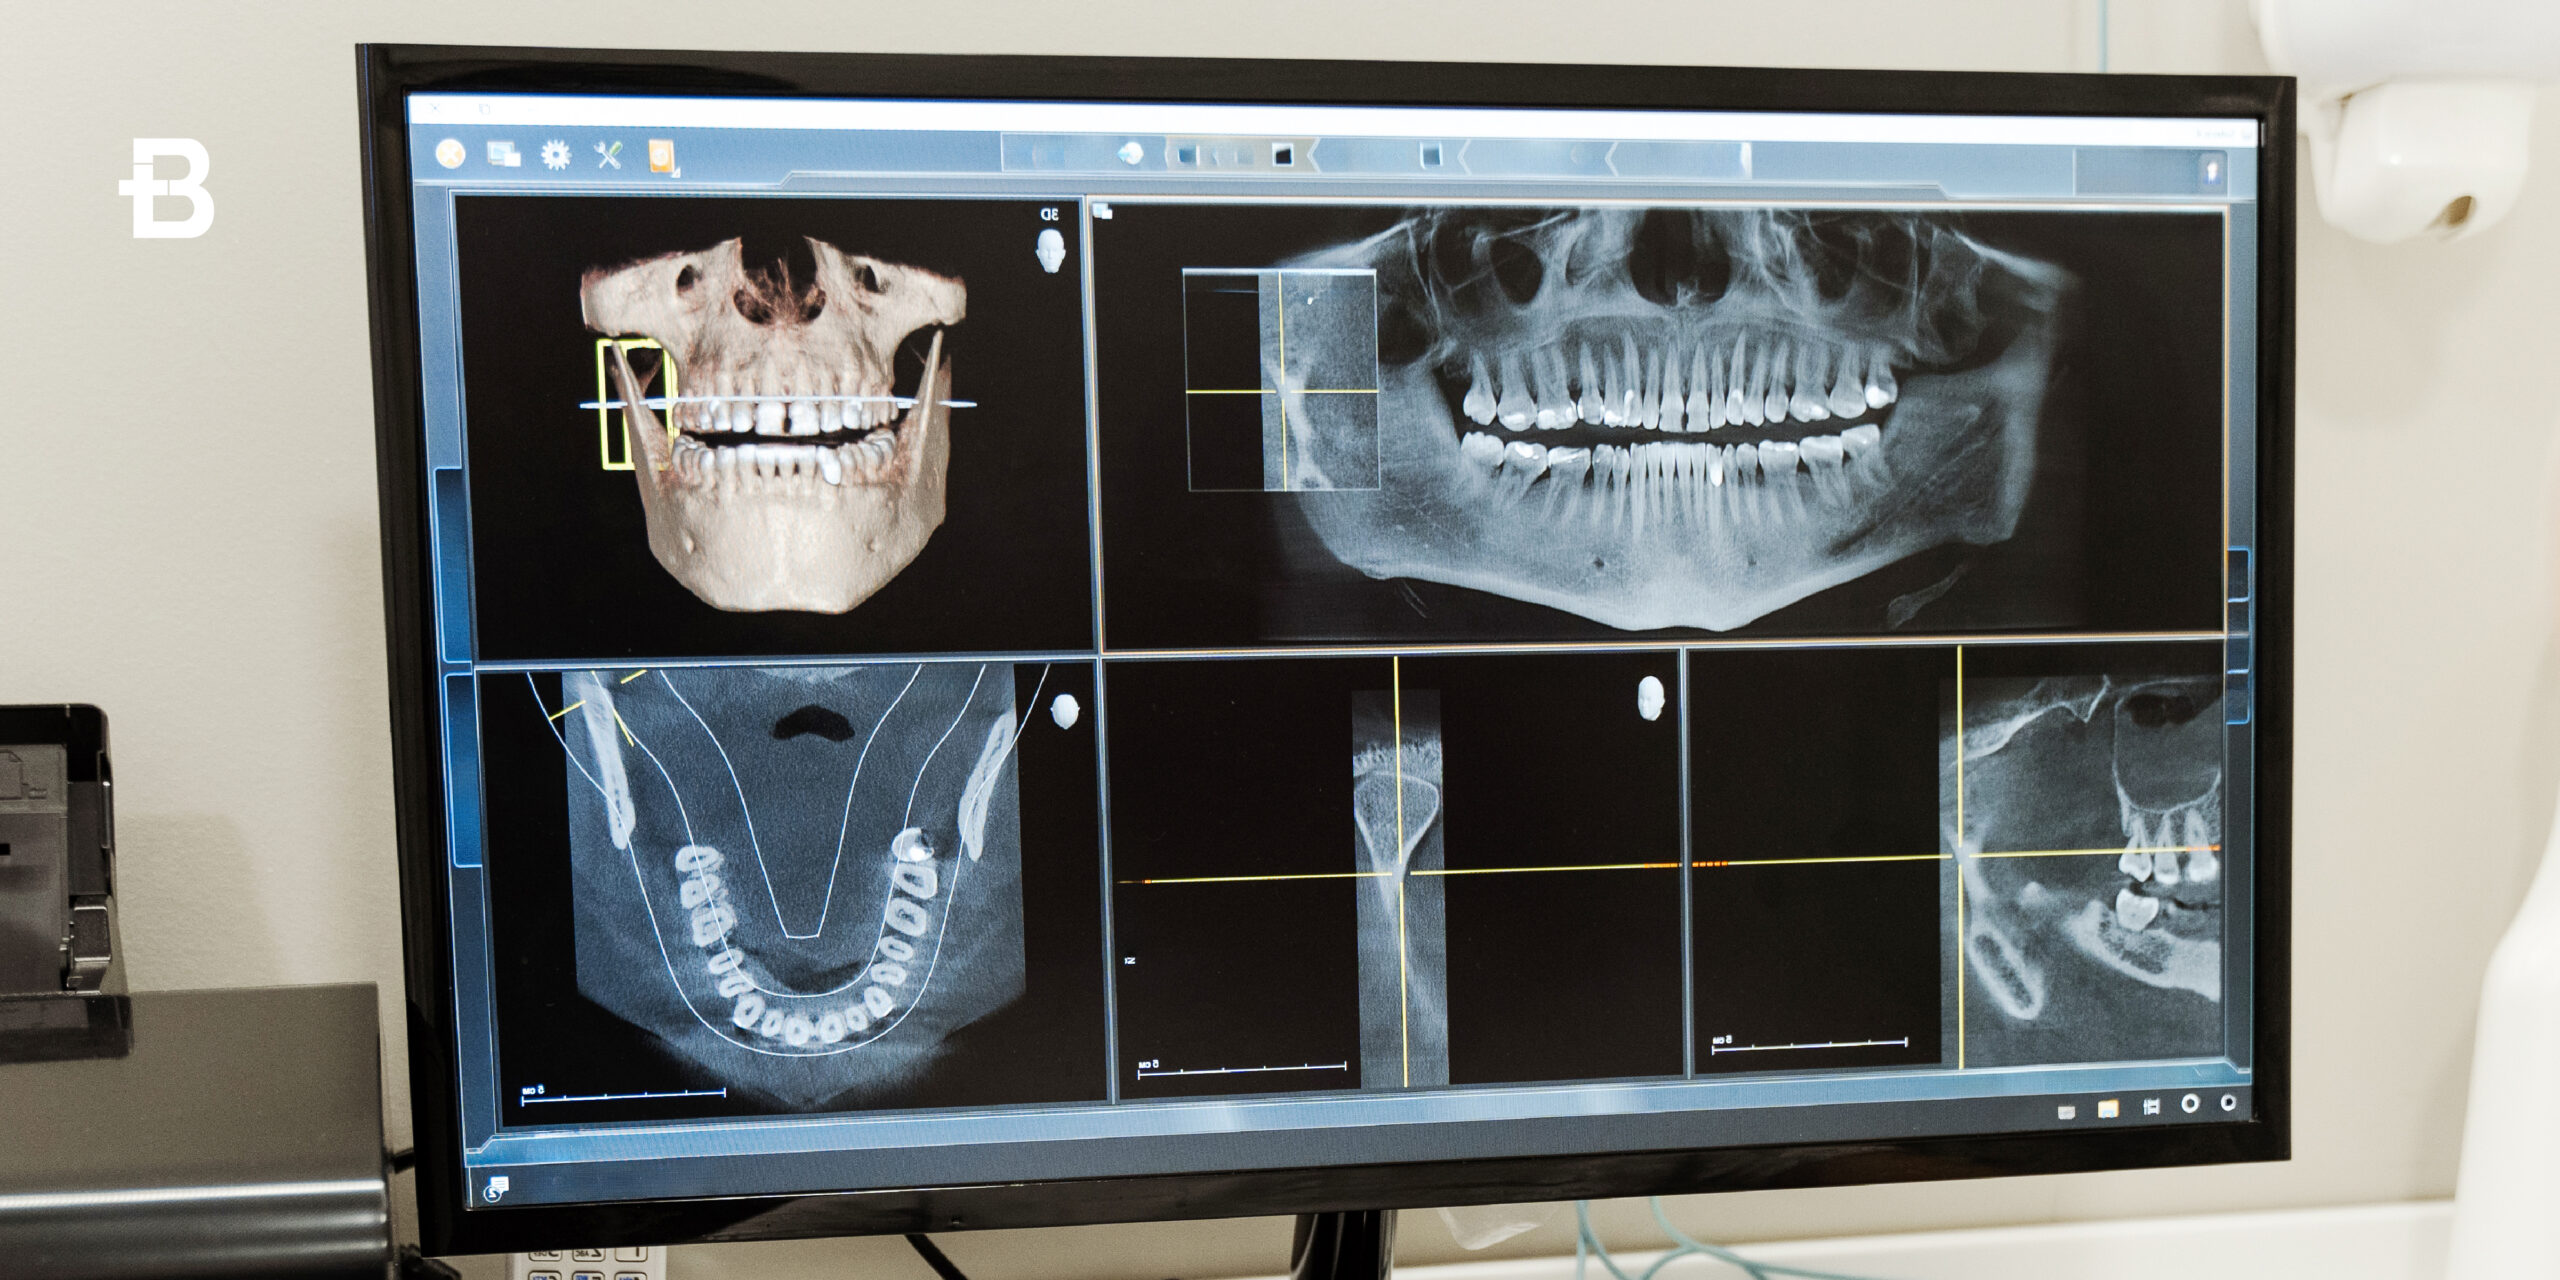

La tecnologia computer guidata ad esempio, permette di progettare l’intervento direttamente sullo schermo grazie a sofisticati software. L’intervento che ne seguirà, nella maggior parte dei casi non prevede tagli o punti di sutura, rendendo l’operazione e la riabilitazione post operatoria molto più agevole. Inoltre è possibile effettuare l’intervento anche in anestesia locale.